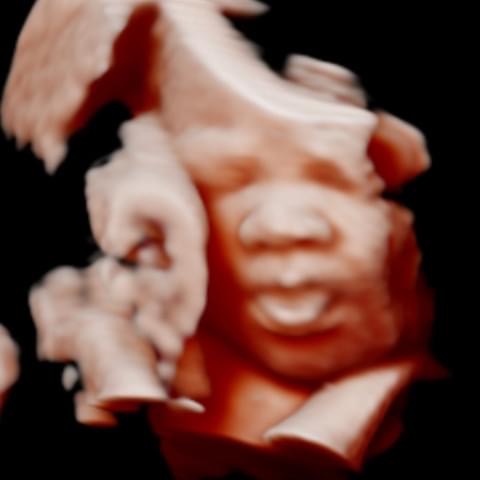

All photos are from our equipment and are of our actual clients.